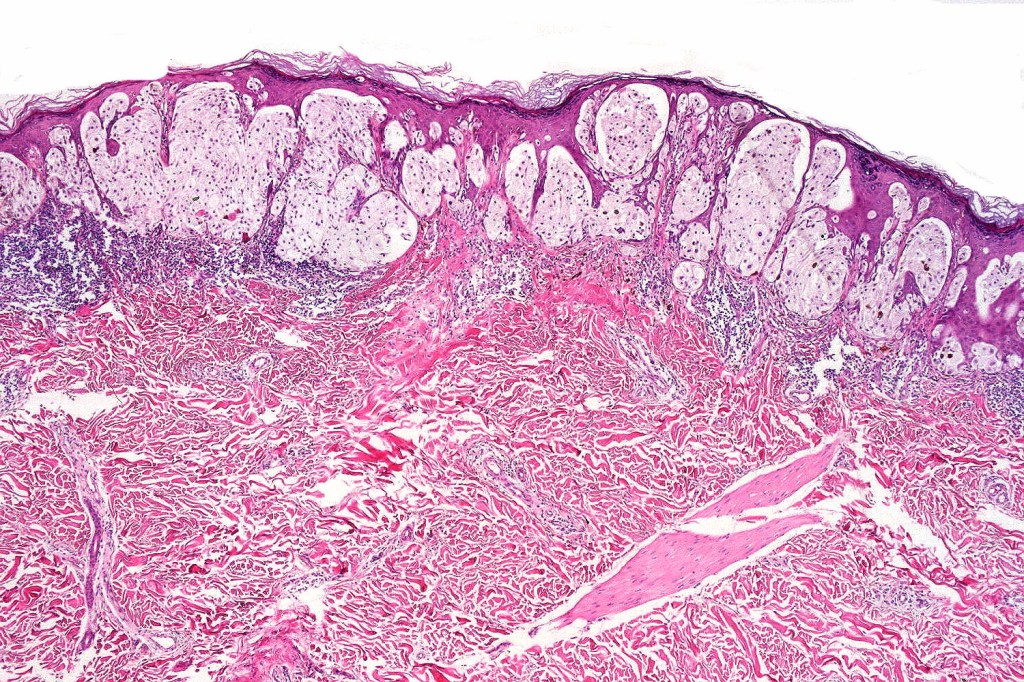

Histological features

•May affect the tumor in part or whole

•Enlarged cells with copious eosinophilic, foamy or clear cytoplasm (some authors include melanoma with clear cell change in the same category)

•Variable pigmentation

•Nuclei vesicular or hyperchromatic

•Pleomorphism is not generally marked and indeed can be very subtle

•Variable mitotic activity